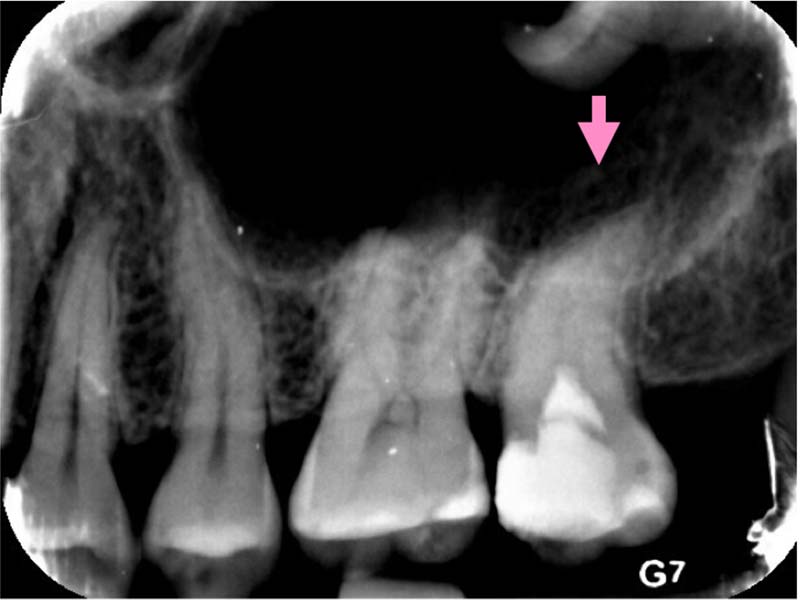

圖例為案例分享:

深度填補過後,持續冷熱敏感

依照症狀及顯微鏡下觀察,移除部分牙隨組織

術後三年追蹤檢查,狀況良好